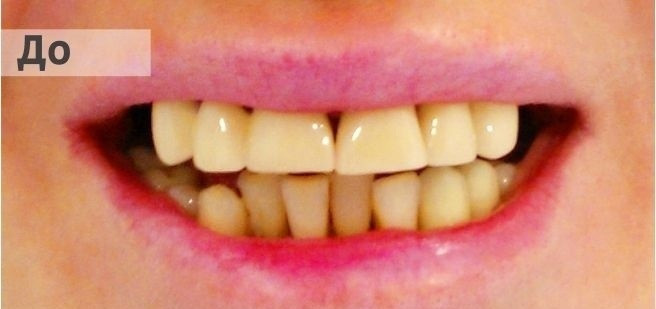

На странице представлено портфолио стоматологий Новосибирска с фото работ до и после имплантации зубов. Мы собрали разные клинические случаи: одиночные импланты, восстановление нескольких зубов и полная реконструкция зубного ряда. Здесь вы можете видеть, как выглядят восстановленные зубы, меняется форма улыбки после процедуры. Изучите результаты до и после имплантации зубов, чтобы оценить качество работы врачей и выбрать стоматологию в Новосибирске, которая поможет вернуть функциональность и эстетику вашей улыбке.

Фотографии до и после: Имплантация